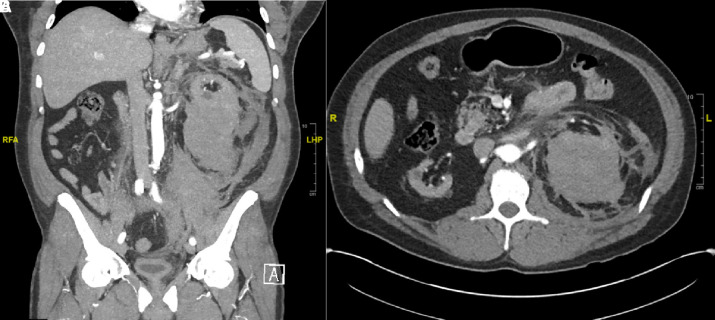

A 45-year-old Hispanic man with diabetes mellitus type 2, hypertension, and ESKD on intermittent hemodialysis since 2017 presented to the hospital with left flank pain. The patient developed left-sided dull flank pain of 1-day duration with associated nausea and vomiting on the day of admission. He denied any recent trauma. Vital signs were remarkable for tachycardia of 115 bpm and a blood pressure of 120/68 mm Hg. Labs demonstrated a decrease in hemoglobin from 12.1 g/dl, 3 weeks before evaluation to 8.6 g/dl. Computed tomography (CT) scan of the abdomen/pelvis with contrast (Figure 1, A and B) showed hemorrhage of the left kidney measuring 6.5×7.2×9.3 cm3. Interval CT angiography did not demonstrate change in the size of the hematoma nor extravasation. Hemoglobin remained stable and he was discharged home to continue outpatient hemodialysis.

Figure 1.

CT scan of the abdomen with intravenous contrast. (A) CT scan of the abdomen (coronal view) shows hemorrhage of the left kidney. (B) CT scan of the abdomen (axial view) demonstrates hemorrhage of the left kidney. CT, computed tomography.